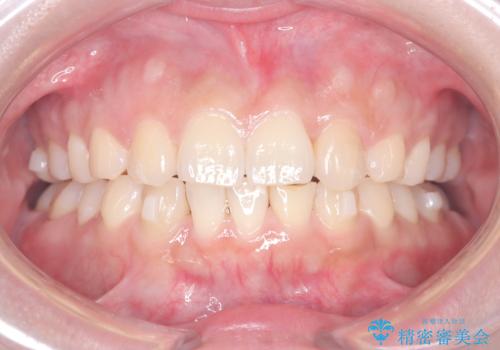

歯のデコボコを治したい! |インビザラインでわずか6ヵ月で矯正完了!

- 「歯の捻じれとがたつき」を主訴に来院された患者様です。

軽度な捻転と叢生だったため、インビザラインのモデレートで治療を行いわずか半年で治療を終える事が出来ました!

目立たないマウスピース矯正【インビザライン】を使用し、

わずか6ヵ月で歯並びがキレイに整いました!